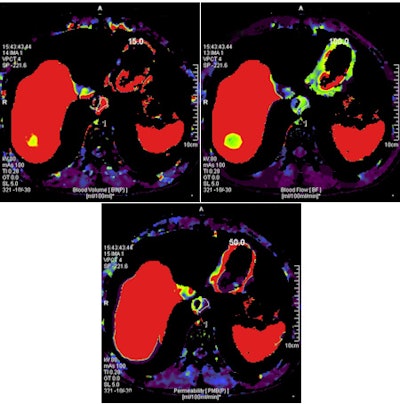

CT perfusion uses various parameters such as blood flow, blood volume, mean transit time, and permeability to demonstrate angiogenesis in tumor tissues and to assess microcircular changes noninvasively and quantitatively, he explained. Angiogenesis is important to the progression and aggressiveness of solid tumors, including esophageal cancer, he told AuntMinnie.com.

"CT perfusion has been used to assess vascularity within tumors in vivo," he said. "It is also possible with CT perfusion to accomplish a quantitative assessment using blood volume, blood flow, and permeability in tumors."

CT perfusion could be preferred for assessing tumor angiogenesis because of its shorter examination time and its utility for quantitative assessment, he said. Therefore, the group developed a research protocol comparing CT perfusion and PET/CT for staging esophageal cancer.

CT perfusion exams included the affected area of the esophagus, and multiple scans were obtained. The calculated average effective radiation dose for the perfusion scans was approximately 9 mSv, and all CT perfusion examinations were performed using a second-generation 256-slice CT scanner.

CT perfusion parameters of blood volume, blood flow, and permeability surface were compared with SUVmax generated from PET, and tumor diagnosis was confirmed histopathologically in all patients. Correlations between tumor grade, pathological cell types, and SUVmax and CT perfusion parameters were assessed.

The study found good correlation between perfusion CT parameters and SUVmax values, but one of its most important findings was the significant difference between stage IV and other stages with respect to blood-flow values on the perfusion CT scans, according to Kantarci.